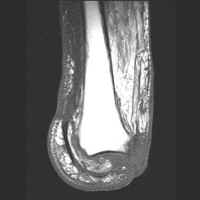

The MRI images below demonstrate the level of the Symes amputation along with bony and

soft tissue changes. Note the thick heel pad forming the majority of the distal

stump: the principle advantage of this procedure due to the more effective weight bearing.